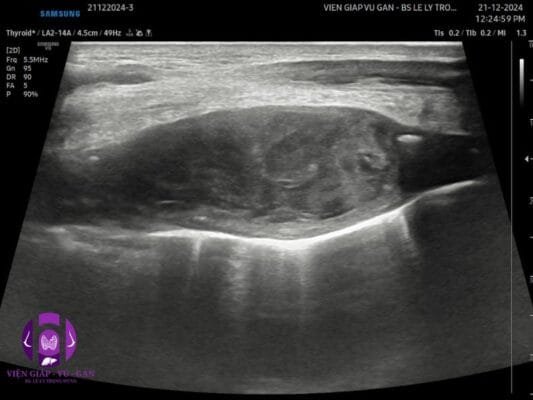

⚡ Vai trò của siêu âm trong chẩn đoán sarcoma mô mềm

Siêu âm là phương tiện chẩn đoán hình ảnh ban đầu quan trọng trong đánh giá khối u mô mềm, đặc biệt là các khối u nông. Phương pháp này có ưu điểm là không xâm lấn, chi phí thấp, thực hiện nhanh chóng và có thể đánh giá động tính chất của khối u (Chiou et al., 2021).

Đặc điểm hình ảnh siêu âm của sarcoma mô mềm:

- Đặc điểm hình thái:

- Khối tăng âm hoặc giảm âm so với mô xung quanh

- Ranh giới thường không đều, có thể có bờ đẩy đi (pseudocapsule)

- Kích thước thường >5cm khi phát hiện

- Hình dạng không đều, thường có dạng bầu dục hoặc đa cạnh

(Gruber et al., 2017)

- Cấu trúc nội bộ:

- Tính chất âm không đồng nhất (heterogeneous)

- Có thể có các vùng hoại tử (vùng vô âm)

- Có thể có canxi hóa (vùng tăng âm với bóng cản)

- Có thể có vùng xuất huyết (vùng giảm âm không đồng nhất)

(Chiou et al., 2021)